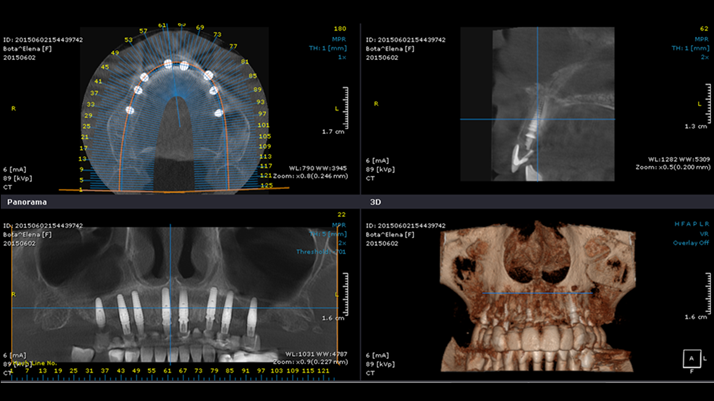

Clinical case: Advantage of fuse abutment with AnyRidge implant for immediate loading in

upper fully edentulous case

- Courtesy of Dr. Kwang Bum Park -

Keywords

AnyRidge, fuse abutment, immediate loading, maxillary fully edentulous case, initial stability, zirconia customized abutments, PMMA temporary bridge, CAD/CAM technique, edentulous, Dr. Kwang Bum Park

Products:

AnyRidge implant system, fuse abutment

“AnyRidge shows excellent initial stability

& stable results after immediate loading in

upper fully edentulous case. ”